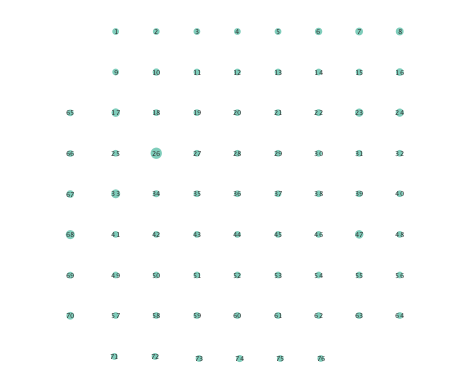

Figure 2 depicts networks inferred from different algorithms for both preictal and ictal intervals of the time series. The figure illustrates results obtained by the linear SVARM, and the K-SVARM approach with and without kernel selection. Each node in the network is representative of an electrode, and it is depicted as a circle, while the node arrangement is forced to remain consistent across the four visual representations. A cursory inspection of the visual maps reveals significant variations in connectivity patterns between ictal and preictal intervals for both models. Specifically, networks inferred via the K-SVARMs, reveal a global decrease in the number of links emanating from each node, while those inferred via the linear model depict increases and decreases in links connected to different nodes. Interestingly, the K-SVARM with kernel selection recovered most of the edges inferred by the linear and the K-SVARM using a polynomial kernel, which implies that both linear and nonlinear interactions may exist in brain networks. Clearly, one is unlikely to gain much insight only by visual inspection of the network topologies. To further analyze differences between inferred networks from both models, and to assess the potential benefits gained by adopting the novel scheme, several network topology metrics are computed and compared in the next subsection.

First, in- and out-degree was computed for nodes in each of the inferred networks. Note that the in-degree of a node counts its number of incoming edges, while the out-degree counts the number of out-going edges. The total degree per node sums the in- and out-degrees, and is indicative of how well-connected a given node is. Figure 3 depicts nodes in the network and their total degrees encoded by the radii of circles associated with the nodes. As expected from the previous subsection, Figures 3 (a) and (b) demonstrate that the linear SVARM yields both increases and deceases in the inferred node degree. On the other hand, the nonlinear SVARM leads to a more spatially consistent observation with most nodes exhibiting a smaller degree after the onset of a seizure (see Figures 3 (c) and (d)), which may imply that causal dependencies thin out between regions of the brain once a seizure starts.